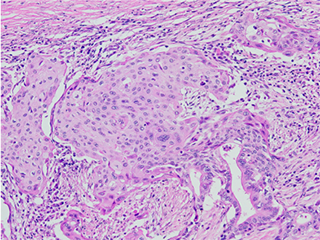

我々は膵腺扁平上皮癌37例を組織学的形態により、膵腺扁平上皮癌NOS(ASC-NOS)症例(図1)とPan-MEC症例(図2)に分類し、両者において融合遺伝子(CRTC1-MAML2及びCRTC3-MAML2)の有無、ムチンコア蛋白(MUC)発現を解析した。

図1[fig.1]